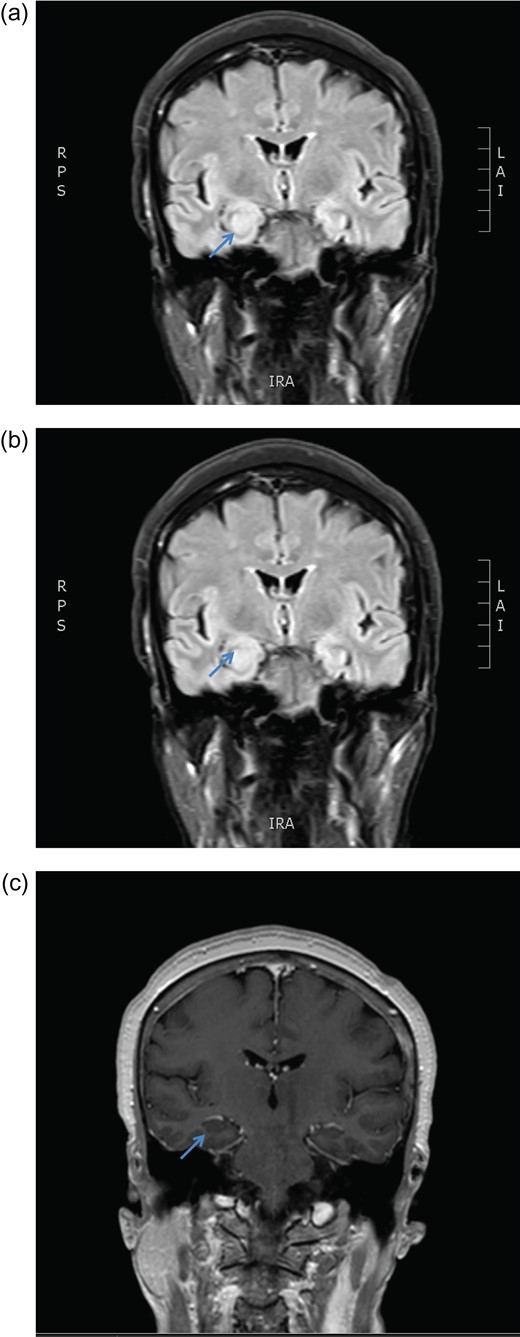

December 2015, she had a normal electroencephalogram (EEG). Subsequent MRI done January and March 2016 showed T2 Weighted Imaging Fluid Attenuated Inversion Recovery (T2WI/FLAIR) changes in the right medial temporal lobe (Fig. 2). Right hippocampal signal change was suspicious of low-grade glioma with a differential diagnosis of post viral limbic encephalitis. There was no enhancement with intravenous gadolinium administration and no other suggestion of a focal malignant disease. She remained clinically well and repeat MRI done October 2016 showed areas of signal abnormalities focused around the posterior horns of the lateral ventricles and but no sign of right temporal lobe low-grade glioma or encephalitis (Fig. 3). All of these signal changes resolved completely with repeated MRI and she had no further seizures.

MRI brain axial T2 FLAIR sequence (October 2016) depicting resolution of right medial temporal lobe high signal but prominence of periventricular hyperintensity in periventricular white matter (arrows).